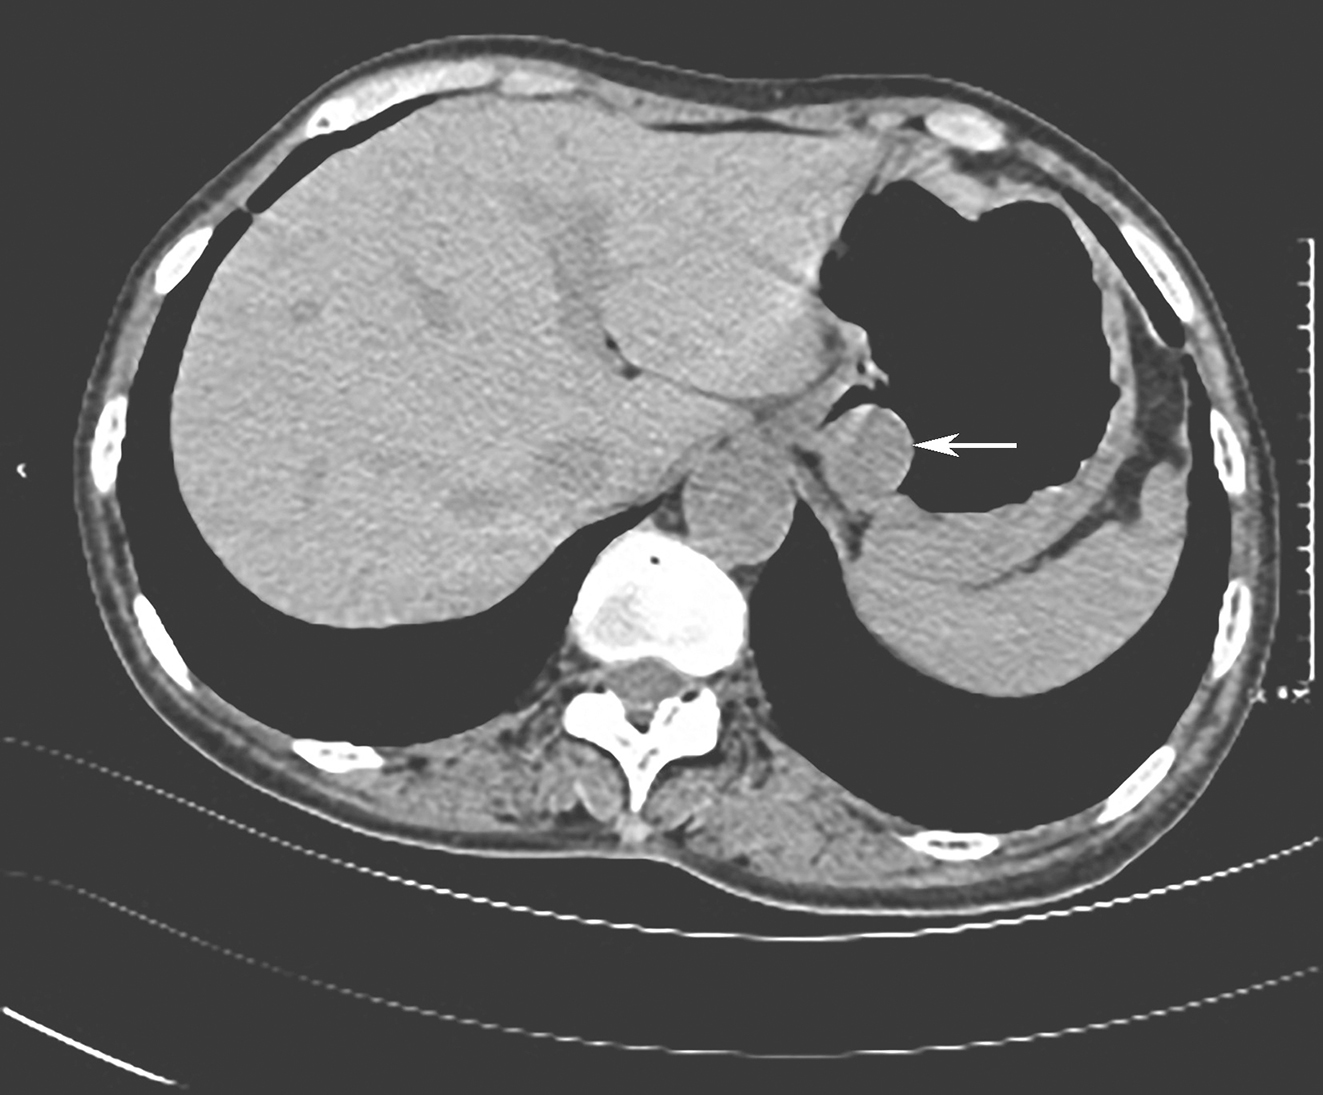

1小时条评论75岁男性,无明显诱因出现反复痰中带血,当地医院给予抗感染、抗结核治疗1个月(具体不详),症状未缓解。患者遂来我院进一步诊治。患者20年前因胃溃疡出血行胃大部切除术,此次咯血是哪里出了问题? 【病情摘要】 1.基本情况 男性患者,75岁,退休教师,因反复...